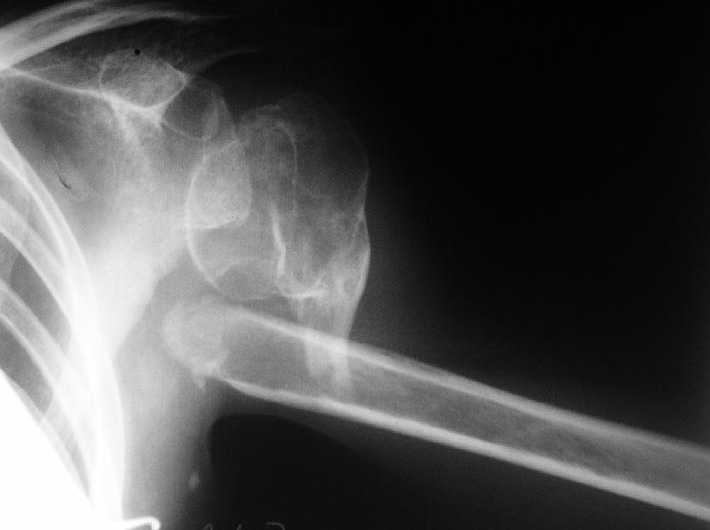

Несращение плеча, деформация головки

Здравствуйте уважаемые коллеги.Помогите, пожалуйста, определиться с тактикой.Больная 40 лет, множественная травма в июне 2007 года. Лечилась в городской больнице.

Повреждение проксимального отдела плеча вели консервативно в гипсовой повязке. В настоящее время больную беспокоят боли в области плечевого сустава, слабость верхней конечности. Амплитуда движений в плечевом суставе в пределах 30-40 градусов. Пациентка хотела бы увеличить объем движений и силу.Движения сейчас в основном за счет ложногго сустава. Варанты - остеосинтез, артролиз, эндопротезирование, оставить как есть. Как-то н один однозначно не привлекает.